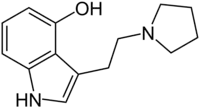

| 4-HO-pyr-T | artificial | 4-OH | (CH2)4 | 3-[2-(Pyrrolidin-1-yl)ethyl]-1H-indol-4-ol | 63097-26-7 | |